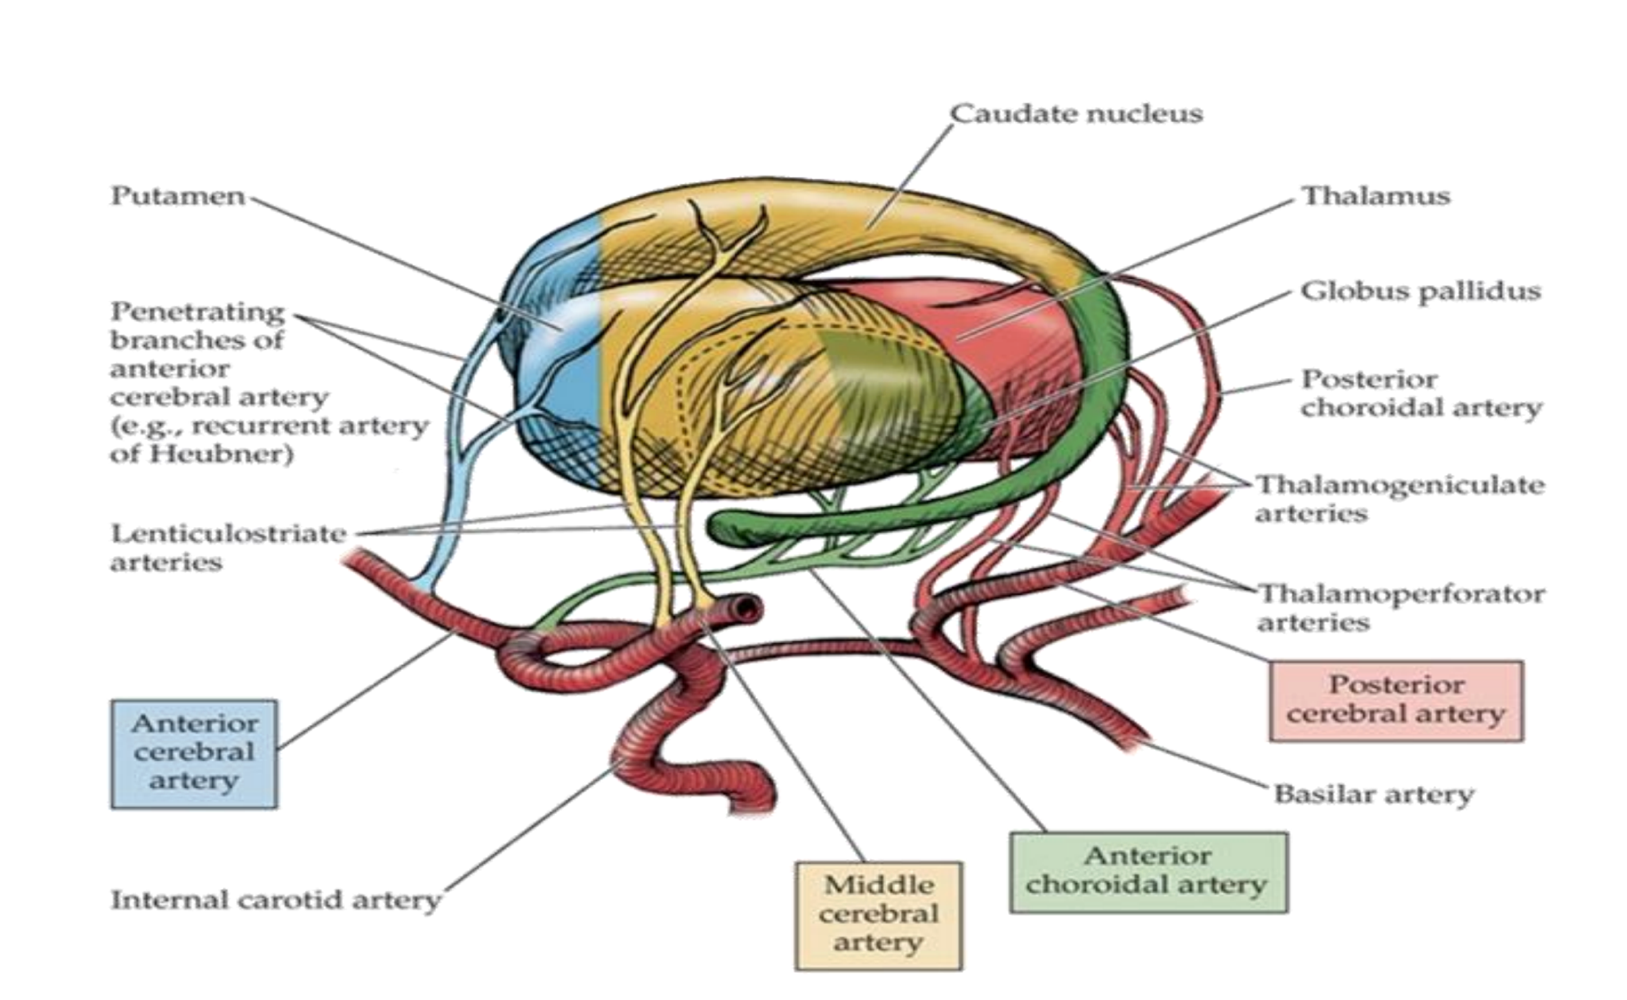

What supplies blood to the caudate nucleus?

Branches from anterior cerebral artery (anterior part)

Boddy of the middle cerebral artery

Tail of the anterior choroidal artery.

What supplies blood to the putamen?

Middle cerebral artery

Branches from anterior cerebral artery (anterior part)

What supplies blood to the globus pallidus?

Lenticular striate arteries

Anterior choroidal of internal carotid & internal capsule

What supplies blood to the thalamus?

Lenticulostriate arteries from the middle cerebral artery